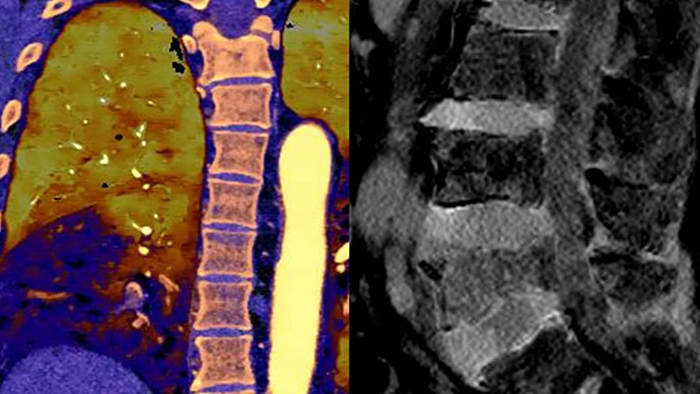

Com os avanços na área das imagens cardíacas e dos exames sem qualquer comprometimento, o Spectral CT 7500 permite obter imagens certas à primeira.

Com os avanços na área das imagens cardíacas e dos exames sem necessidade de qualquer trade-off, o Spectral CT 7500 permite obter as imagens ideais e necessárias com um único exame.

O modo espectral está sempre ativo para que cada exame seja entregue com resultados convencionais e espectrais.